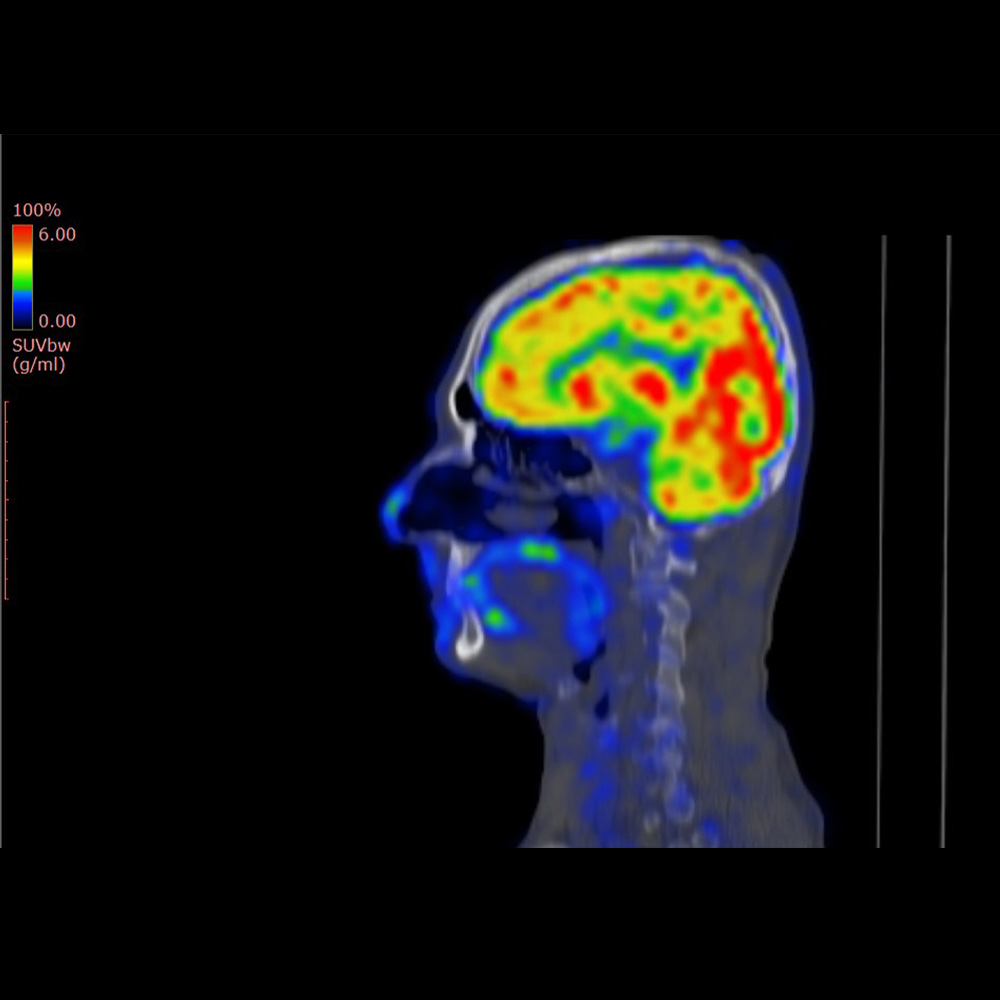

One of the primary imaging techniques used for amyloid detection is positron emission tomography (PET). During a PET scan, a small amount of a radioactive tracer is injected into the patient’s bloodstream. This tracer binds to amyloid plaques in the brain, emitting signals that are captured by the PET scanner. This information is then used to generate detailed images of amyloid distribution in the brain.

Amyloid brain imaging, also known as an amyloid PET scan, is a specialized exam that detects the presence of amyloid plaques in the brain. Amyloid plaques are commonly associated with Alzheimer’s disease and other neurodegenerative conditions. This imaging study provides important diagnostic information that helps referring providers evaluate the possible causes of cognitive impairment or memory loss.

Amyloid brain imaging helps determine whether amyloid plaques are present in the brain. This information can assist providers in distinguishing Alzheimer’s disease from other causes of cognitive decline. Results are interpreted alongside a patient’s medical history, cognitive testing, laboratory studies, and other imaging exams to support informed clinical decision-making.